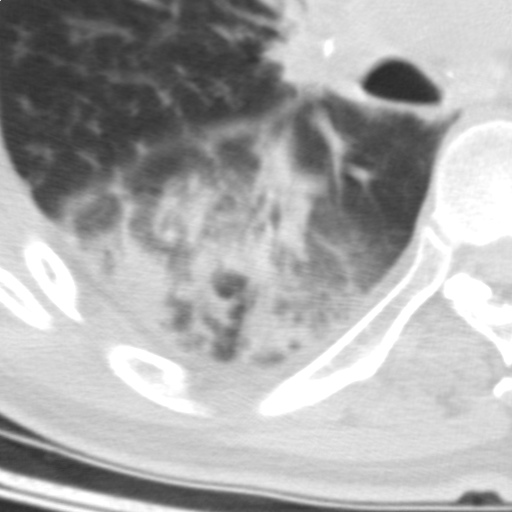

以下是引用随光逐影在2009-5-1 13:53:00的发言:[br]考虑为:1)两肺血行播散型肺结核;2)右肺下叶炎症感染。3)右侧胸膜增厚。